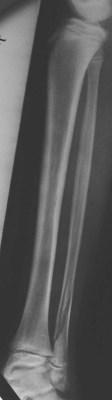

Salter 2